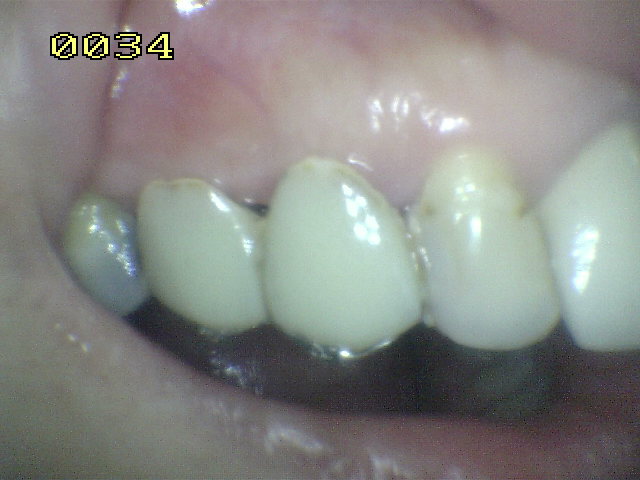

Observe la adaptación del metal al esmalte de este puente Maryland  que repone la pieza dental 24